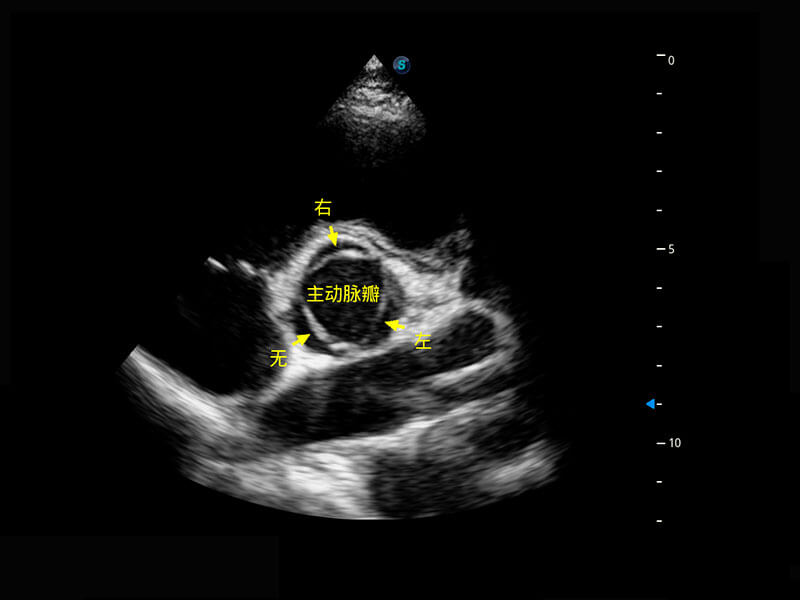

• 新生儿心脏